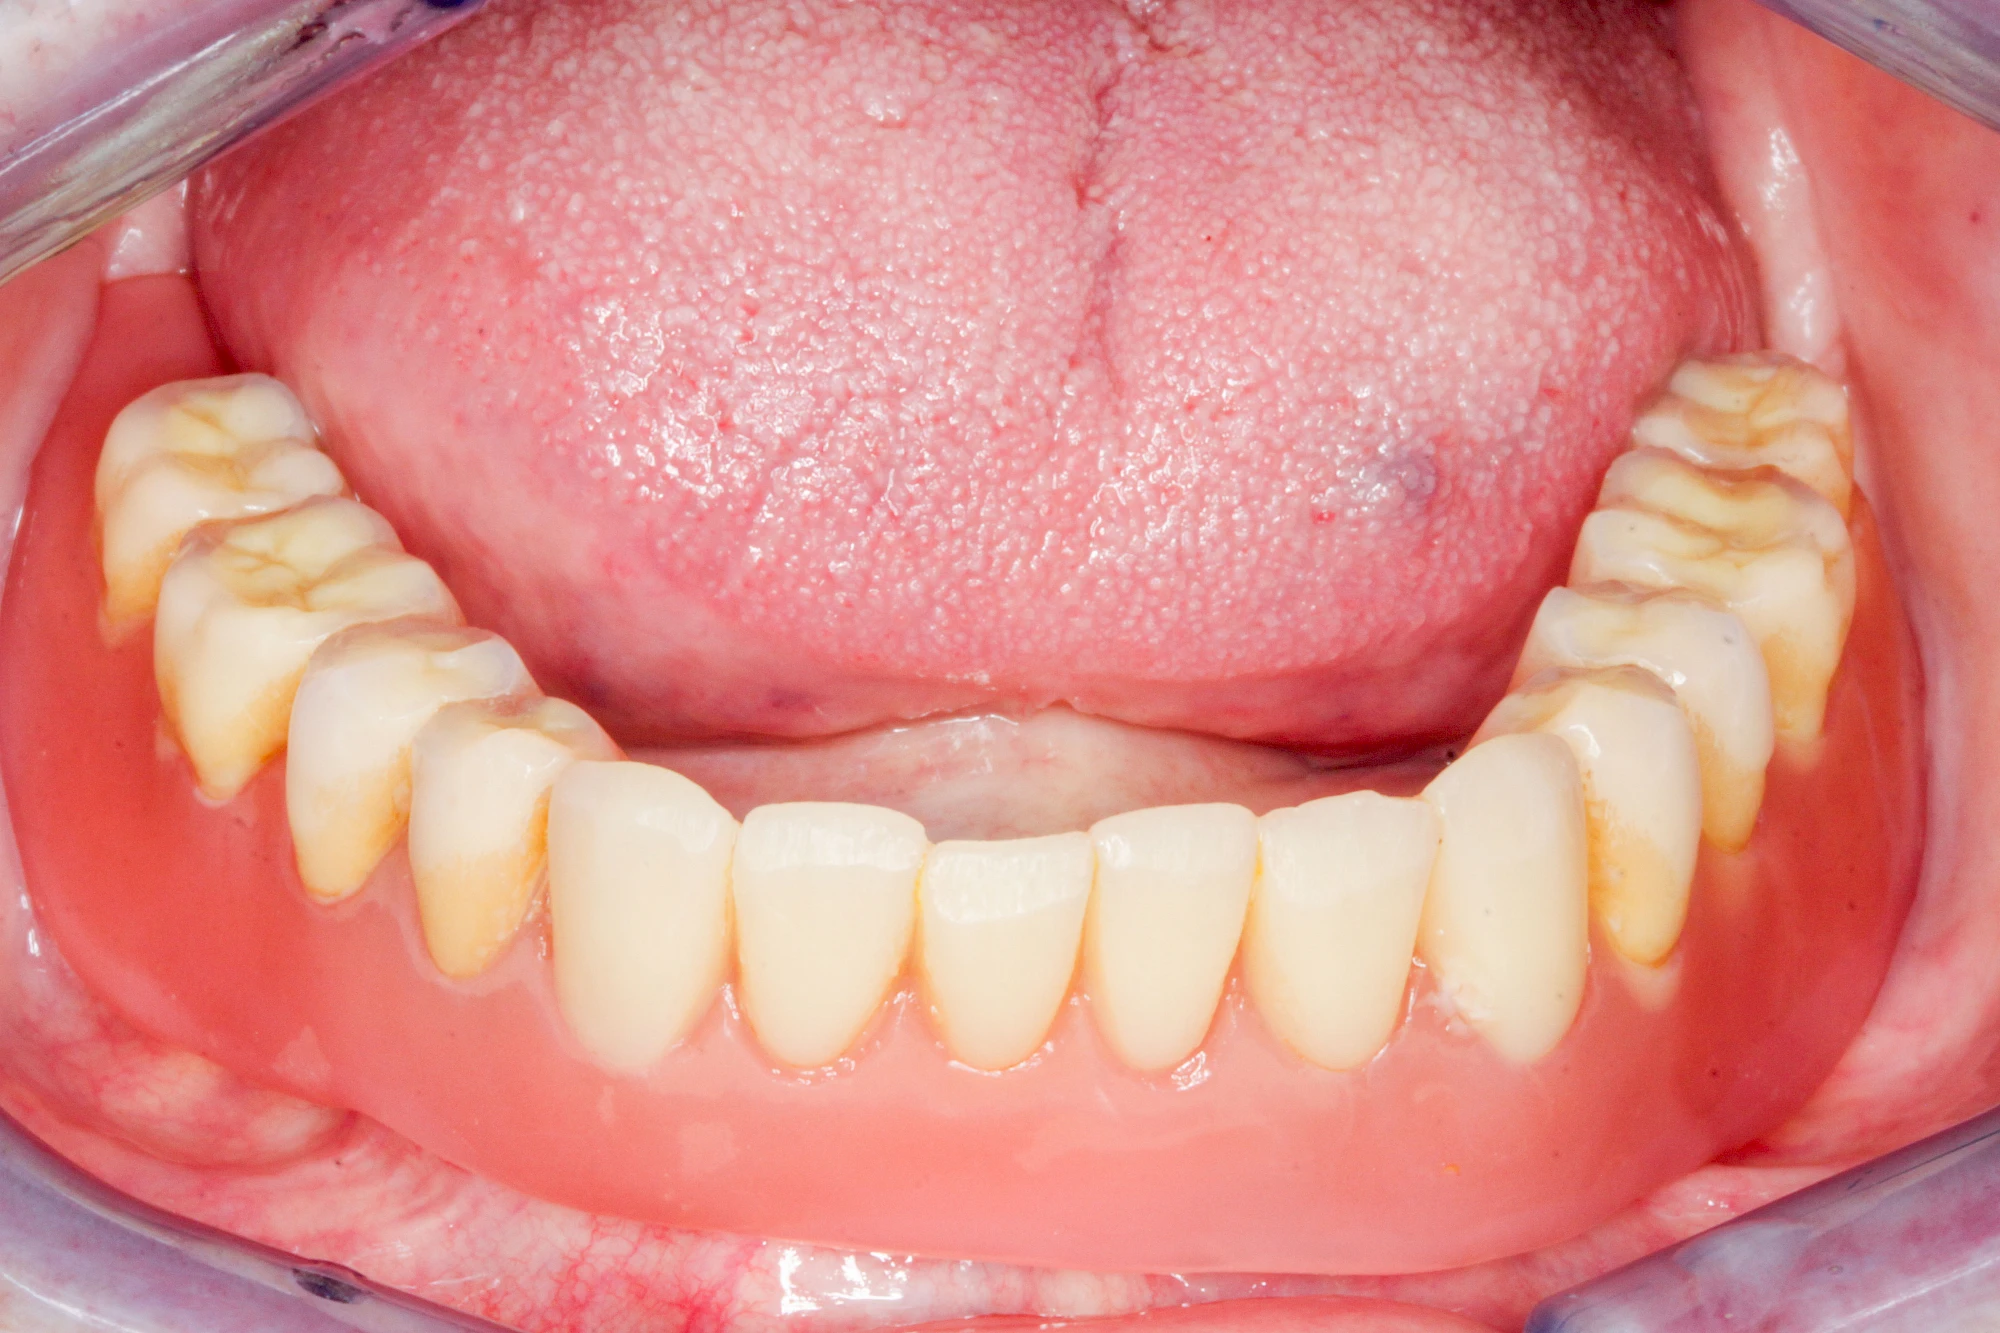

Implantate: Prothesen

Bei herausnehmbaren Prothesen werden Implantate eingesetzt, um den Halt und den Tragekomfort der Prothesen zu verbessern. Dazu kommen verschiedene Verbindungselemente zum Einsatz:

- Teleskope

- Kugelköpfe

- Tellerförmige Lokatoren

- Stege

- Magnete (selten)

Neben rein implantat-getragenen zahnärztlichen Versorgungen werden bei herausnehmbaren Prothesen Implantate auch in Sinne einer "strategischen Pfeilervermehrung" ergänzend zu eigenen Zähnen zur Verankerung eines Zahnersatzes genutzt.

Varianten zur Verankerung von abnehmbarem Zahnersatz auf Implantaten